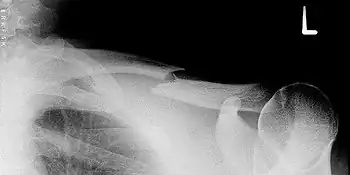

Épaule, ceinture scapulaire et humérus

Fracture de la clavicule

Cette fracture est extrêmement fréquente et intéresse environ 5 % des entrants aux urgences hospitalières. Elle a lieu le plus souvent au tiers moyen de la diaphyse. Elle peut survenir chez le nouveau-né à la suite d'un accouchement difficile (fracture obstétricale).